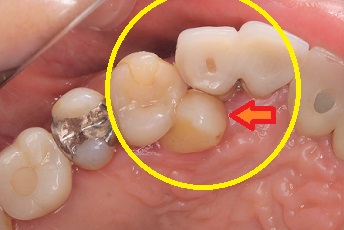

赤い矢印が犬歯です。歯が重なり合っているので食渣が詰まりやすい

状態です。